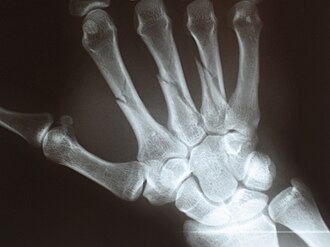

Kosti zapešća (lat. ossa metacarpalia I-V) ili metakarpalne kosti su pet kostiju u šaci čovjeka, smještenih između kostiju članaka prstiju i kosti pešća. Kosti zapešća čine zapešće (lat. Metacarpus).

Metakarpalne kosti su po obliku duge kosti, koje se sastoje od trupa na čijem kraju su zadebljanja, baza (lat. basis) i glava (lat. caput). Na proksimalnom kraju nalazi se baza metakarpalne kosti uzglobljena sa kostima pešća, dok se na distalnom kraju svake metakarpalne kosti, uzglobljen sa proksimalnim člankom odgovarajućeg prsta, nalazi se glava metakarpalne kosti.

Kosti pešća obilježavaju se rednim brojevima, tako da se kost koja se veže na proksimalan članak palca označava brojem jedan, i tako redom do pete kosti pešća koja se veže na peti "mali" prst. Kosti pešća služe kao polaziše i hvatiše mišića šake.

Kod čovjeka, distalni dio svake metakarpalne (MC) kosti uzglobljen je se proksimalnim člankom odgovarajućeg prsta u metakarpofalangealnim zglobovima (I-V), dok je proksimalni dio:

- prve metakarpalne kosti zapešća uzglobljena je sa trapeznom kosti (lat. os trapezium),

- druge metakarpalne kosti uzglobljen je sa trapeznom, trapezoidnom kosti (lat. os trapezoideum), glavičastom kosti (lat. os capitatum) i proksimalnim dijelom treće metatarzalne kosti

- treće metakarpalne kosti uzglobljen je sa glavičastom kosti, te proksimalnim dijelovima druge i četvrte MC kosti

- četvrte metakarpalne kosti uzglobljen je sa glavičastom kosti i kukastom kosti (lat. os hamatum), te proksimalnim dijelom treće i pete MC kosti

- pete metakarpalne kosti uzglobljen je sa kukastom kosti i proksimalnim dijelom četvrte MC kosti